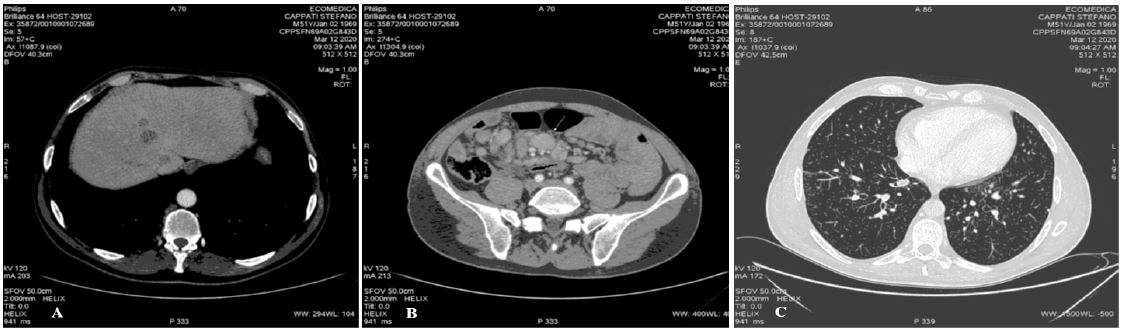

Complete blood cell count indicated increased WBC (28.000/mm3, with neutrophilia), and platelet count (577.000/mm3), high levels of lactate dehydrogenase (LDH) (636 mU/ml), B2-microglobulin (3,84 mg/L) and C-reactive protein (8,94 mg/L). This inflammatory state rapidly improved with steroid pre-phase treatment. Ann-Arbor staging was IVa (Figure 1).

Figure 1: Baseline CT-scan: hepatic lesions (a), abdomen lymphadenopathy (b), lung lesions (c).